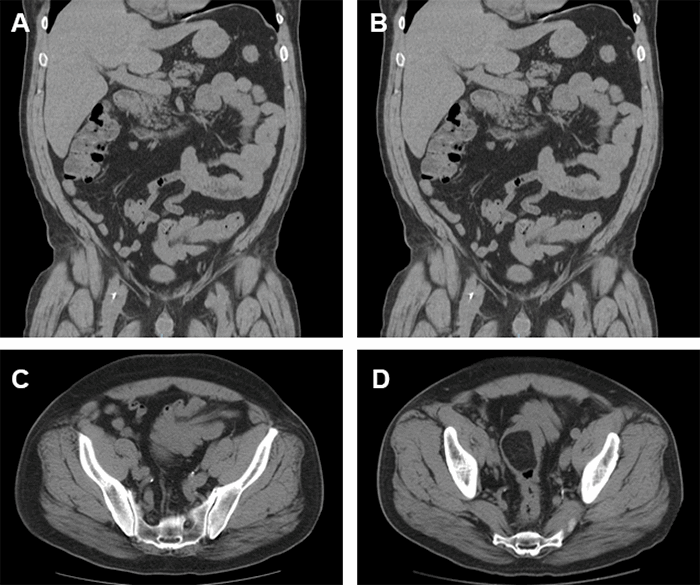

We report a case of a 57-year-old man who presented to an outlying emergency department with a six-day history of progressive and intermittent lower abdominal pain. This pain was accompanied by nausea without vomiting, fevers, and chills. He developed blood in his stool two days prior to assessment, including the morning of presentation. He denied any symptoms of anemia, such as fatigue or shortness of breath. His lower abdomen was tender to palpation with no palpable masses, rebound tenderness, or guarding. His medical history included hypertension, rheumatoid arthritis, and benign prostatic hypertrophy. The patient had undergone two prior colonoscopies revealing only benign polyps, the most recent of which was five years ago. Laboratory investigations, including complete blood count and comprehensive metabolic panel, were unremarkable. Computed tomography (CT) scan of the abdomen and pelvis demonstrated sigmoid intussusception with a 4.4 cm × 3.1 cm fat density intraluminal sigmoid mass (Figure 1). He was transferred to our facility for further evaluation and treatment by the colorectal surgery team.

Figure 1. CT Scan of Abdomen and Pelvis. Published with Permission

A) Coronal view of intussusception involving the proximal, mid, and distal portions of sigmoid colon; B) Coronal view of a fat density intraluminal polyp, 4.4 cm × 3.1 cm in size, in mid and distal sigmoid colon; C) Axial view of intussusception involving proximal, mid and distal portions of sigmoid colon; D) Axial view of fat density intraluminal polyp, 4.4 cm × 3.1 cm in size, in mid and distal sigmoid colon